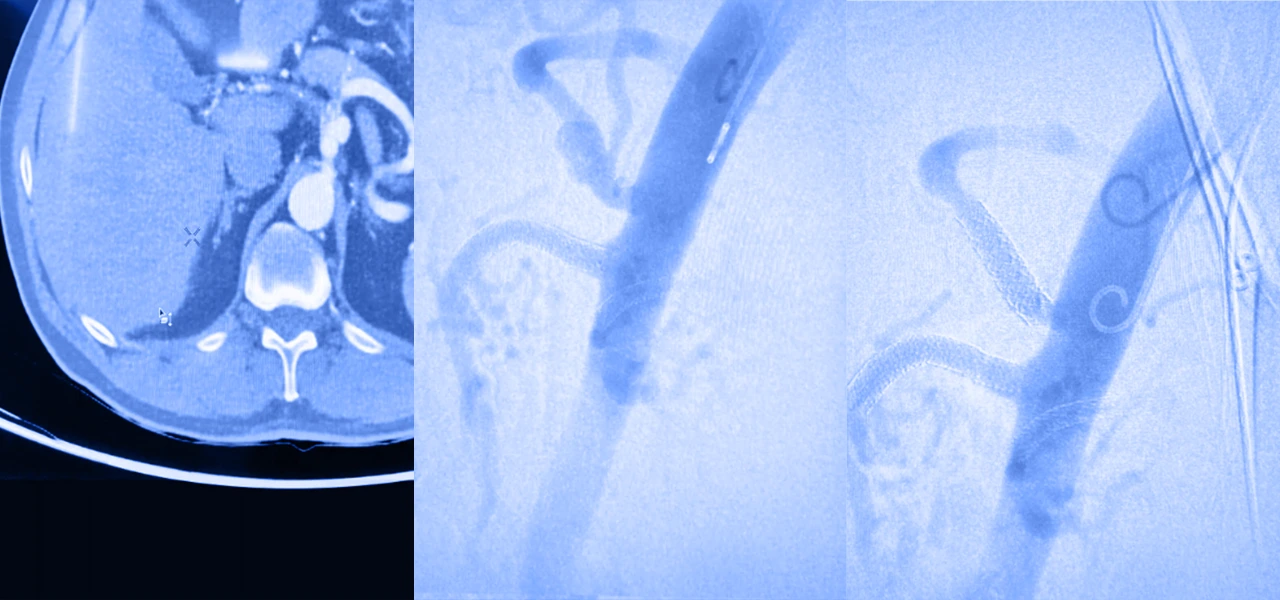

Los aneurismas de arterias periféricas generalmente se diagnostican con un buen examen físico. Algunos estudios como la ecografía dúplex y una angiotomografía pueden confirmar su presencia.

Pero en aneurismas grandes, cuando miden por arriba de dos centímetros, que están creciendo de manera rápida o que causan síntomas, la intervención es necesaria. La cirugía abierta es el principal tratamiento y permite extirpar la sección dañada de la arteria, para reemplazarla con un injerto.

También existe la posibilidad de reparación endovascular, un enfoque menos invasivo, que consiste en insertar un catéter a través de la arteria para colocar un stent que fortalecerá la pared de la arteria y desviará el flujo sanguíneo del aneurisma.